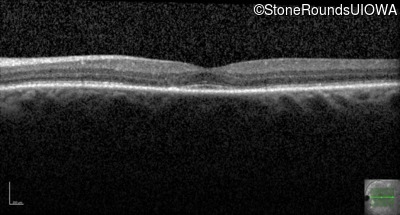

This 44 year old man became photophobic about 6 years ago. He has been taking Imuran since his kidney transplant 23 years ago.

| Senior-Loken Syndrome | NPHP1 | Gly343Arg G(GG)>A(GG) | Deletion of Entire Gene | AR |